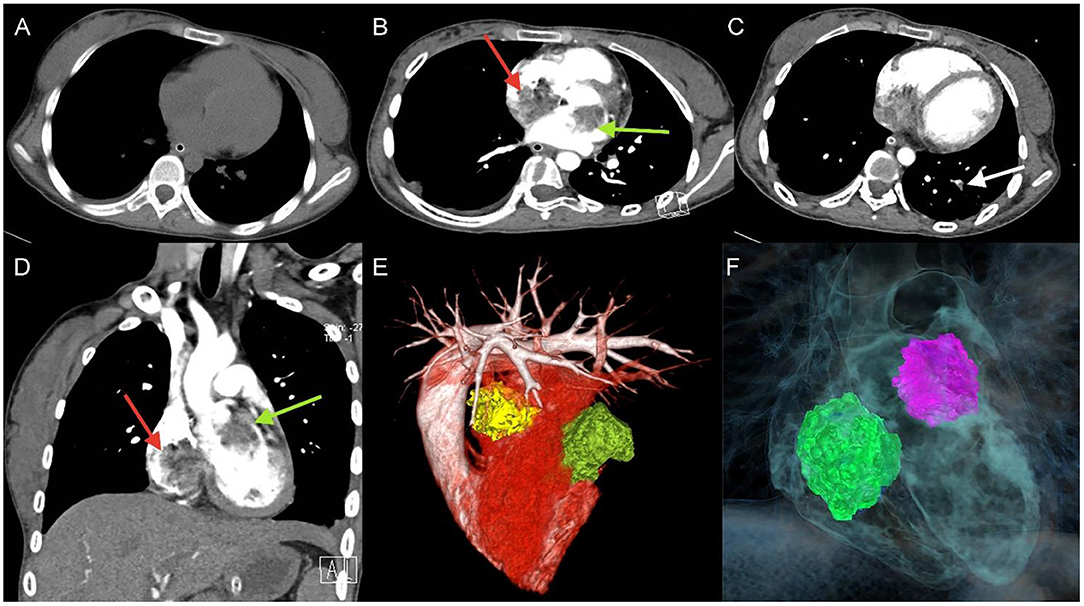

A 17-year-old girl presented to our hospital on August 22, 2021 with clouding of consciousness for more than 3 days. At 3+days prior, the patient was unable to speak the patient was unable to speak when called softly and unable to open the right eye, combined with involuntary movements of the limbs and incontinence. The patient visited the local hospital immediately, where relevant tests were performed, suggesting intracranial lesions. Since the specific treatment measures were unavailable at the previous hospital, she was transferred to our hospital for further treatment. There was no history of trauma or familial genetic diseases, such as high blood pressure and diabetes. Physical examination revealed a body temperature of 37.0°C, heart rate of 110 bpm, regular heart rhythm, blood pressure of 113/77 mmHg, and no pathological murmurs in the valve region; pulmonary auscultation revealed coarse rales in the entire lung. The pupils were equal, round, and pupillary light reflexes were delayed. Both lower limbs exhibited hypertonia and hyperreflexia of the knee and tendon reflexes. Laboratory examinations revealed the following levels (normal range): coagulation function test showed D-dimer was 0.57 mg/L (< 0.5 mg/L) and fibrinogen was 5.82 g/L (2.00–4.00 g/L). Routine blood tests showed that the absolute value of neutrophils was 7.38 × 109/L (1.8 × 109/L−6.3 × 109/L). Infection-related markers showed that the hypersensitive C-reactive protein level was 111.563 mg/L (0.068–8.200 mg/L). Creatine kinase, α-hydroxybutyrate dehydrogenase, and lactate dehydrogenase levels were 148 U/L (26–140 U/L), 218 U/L (90–180 U/L), and 295 U/L (140–271 U/L), respectively. Computed tomography pulmonary angiography (CTPA) detected filling defects in the right atrium, left atrium, and left lower pulmonary basilar artery (Figure 1), and a diagnosis of Pulmonary embolism was made. Transthoracic echocardiography (TTE) revealed irregular iso-echoic masses in the bilateral atrium that were likely myxomas, given their location and appearance in a young patient; the myxoma in the left atrium measured approximately 38 × 21 mm, and it was attached to the junction of the lower part of the interatrial septum (IAS) and the root of the anterior mitral leaflet; in the right atrium it measured approximately 51 × 27 mm, and it was attached to the lower part of the IAS (Figure 2A). These masses resulted in the acceleration of the tricuspid valve antegrade flow (Figure 2B). Craniocerebral computed tomography (CT) showed extensive hypodensity in the bilateral parts of the pons and patchy hypodensity in the left corona radiata area and bilateral basal ganglia areas. Magnetic resonance imaging (MRI) also revealed extensive hypointensity on T1-weighted imaging and hyperintensity on T2-weighted imaging in the bilateral parts of the pons, and a patchy hyperintensity on T2-weighted imaging in the bilateral basal ganglia areas; bilateral centrum semiovale; and right frontoparietal lobe, which presented as high signal on diffusion-weighted imaging (DWI) (Figure 3). This confirmed the diagnosis of brain ischemia. To prevent thrombosis, low molecular weight heparin calcium (subcutaneous injection, 0.4 ml/12 h) was commenced on the second day of admission and continued until discharge. The patient underwent successful removal surgery for a biatrial myxoma. The masses were sent for histological examination, which confirmed the presence of a myxomatous matrix containing myxoma cells (Figure 4). The patient recovered uneventfully and was discharged 9 days after the procedure. The patient has been followed-up postoperatively for over 2.5 months, and limb motor function of the patient has recovered to some degree, but there is intellectual and cognitive decline.

Figure 1. Unenhanced thoracic CT (A), axial and coronal views of Computed tomography pulmonary angiography (CTPA) detected filling defects in right atrium (red arrow), left atrium (green arrow) (B,D), and left lower pulmonary basilar artery (white arrow) (C), three-dimensional reconstruction of heart (E) and (F) corresponding schematic illustration demonstrating the biatrial myxoma.

Pulmonary embolic events are rare, but when they occur, it is important to identify the source of the embolus, and in previous reviews of the literature, the majority of emboli originated from deep venous thrombosis (DVT), accounting for about 50–70%. In addition to DVT, cancer-related emboli are also quite common (19). Clinically significant embolic events are uncommon in patients with atrial myxoma. However, in cases of right atrial or right ventricular myxoma, embolectomy of tumor fragments into the pulmonary vasculature with subsequent pulmonary hypertension has been reported (14). In the early stages of pulmonary embolism, the clinical symptoms and imaging manifestations are atypical, and it is easy to misdiagnose pulmonary embolism as pneumonia; however, the role of non-contrast chest CT scans in the diagnosis of pulmonary embolism is limited; currently, the preferred technique for the diagnosis of pulmonary embolism is CTPA, which can detect filling defects in the pulmonary circulation and help to confirm the diagnosis of pulmonary embolism, and it is clinically important to assess the severity of a patient's pulmonary embolism based on the results of CTPA (20). In our case, infiltrates were seen in the posterior basal segment of the left lower lung lobe on non-contrast chest CT and the patient was diagnosed with pneumonia; subsequent CTPA clearly showed the infiltrates to be filling defects of the pulmonary artery.